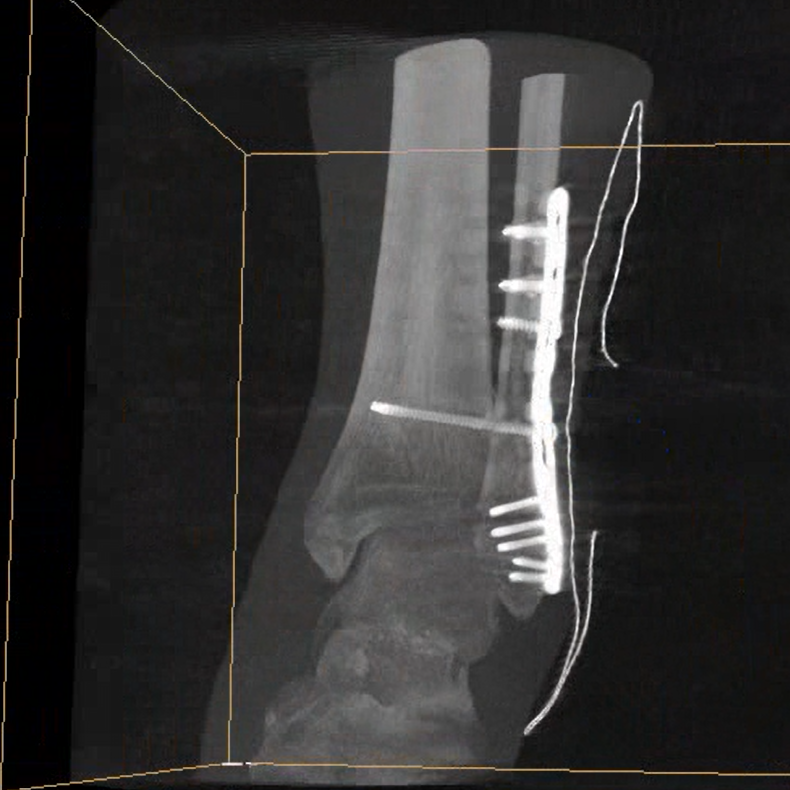

術(shù)中三維成像和橫斷面圖像提供多角度的手術(shù)診斷信息,輔助醫(yī)生進(jìn)行術(shù)中評(píng)估判斷,諸如骨折復(fù)位情況和內(nèi)植入螺釘?shù)某叽绾臀恢?,輔助手術(shù)更好地完成。

在C臂掃描過程中,始終保持拍攝主體處于射線束的中心,避免了序列圖像采集過程中的橫縱方向運(yùn)動(dòng),減少相對(duì)運(yùn)動(dòng)造成的運(yùn)動(dòng)偽影。